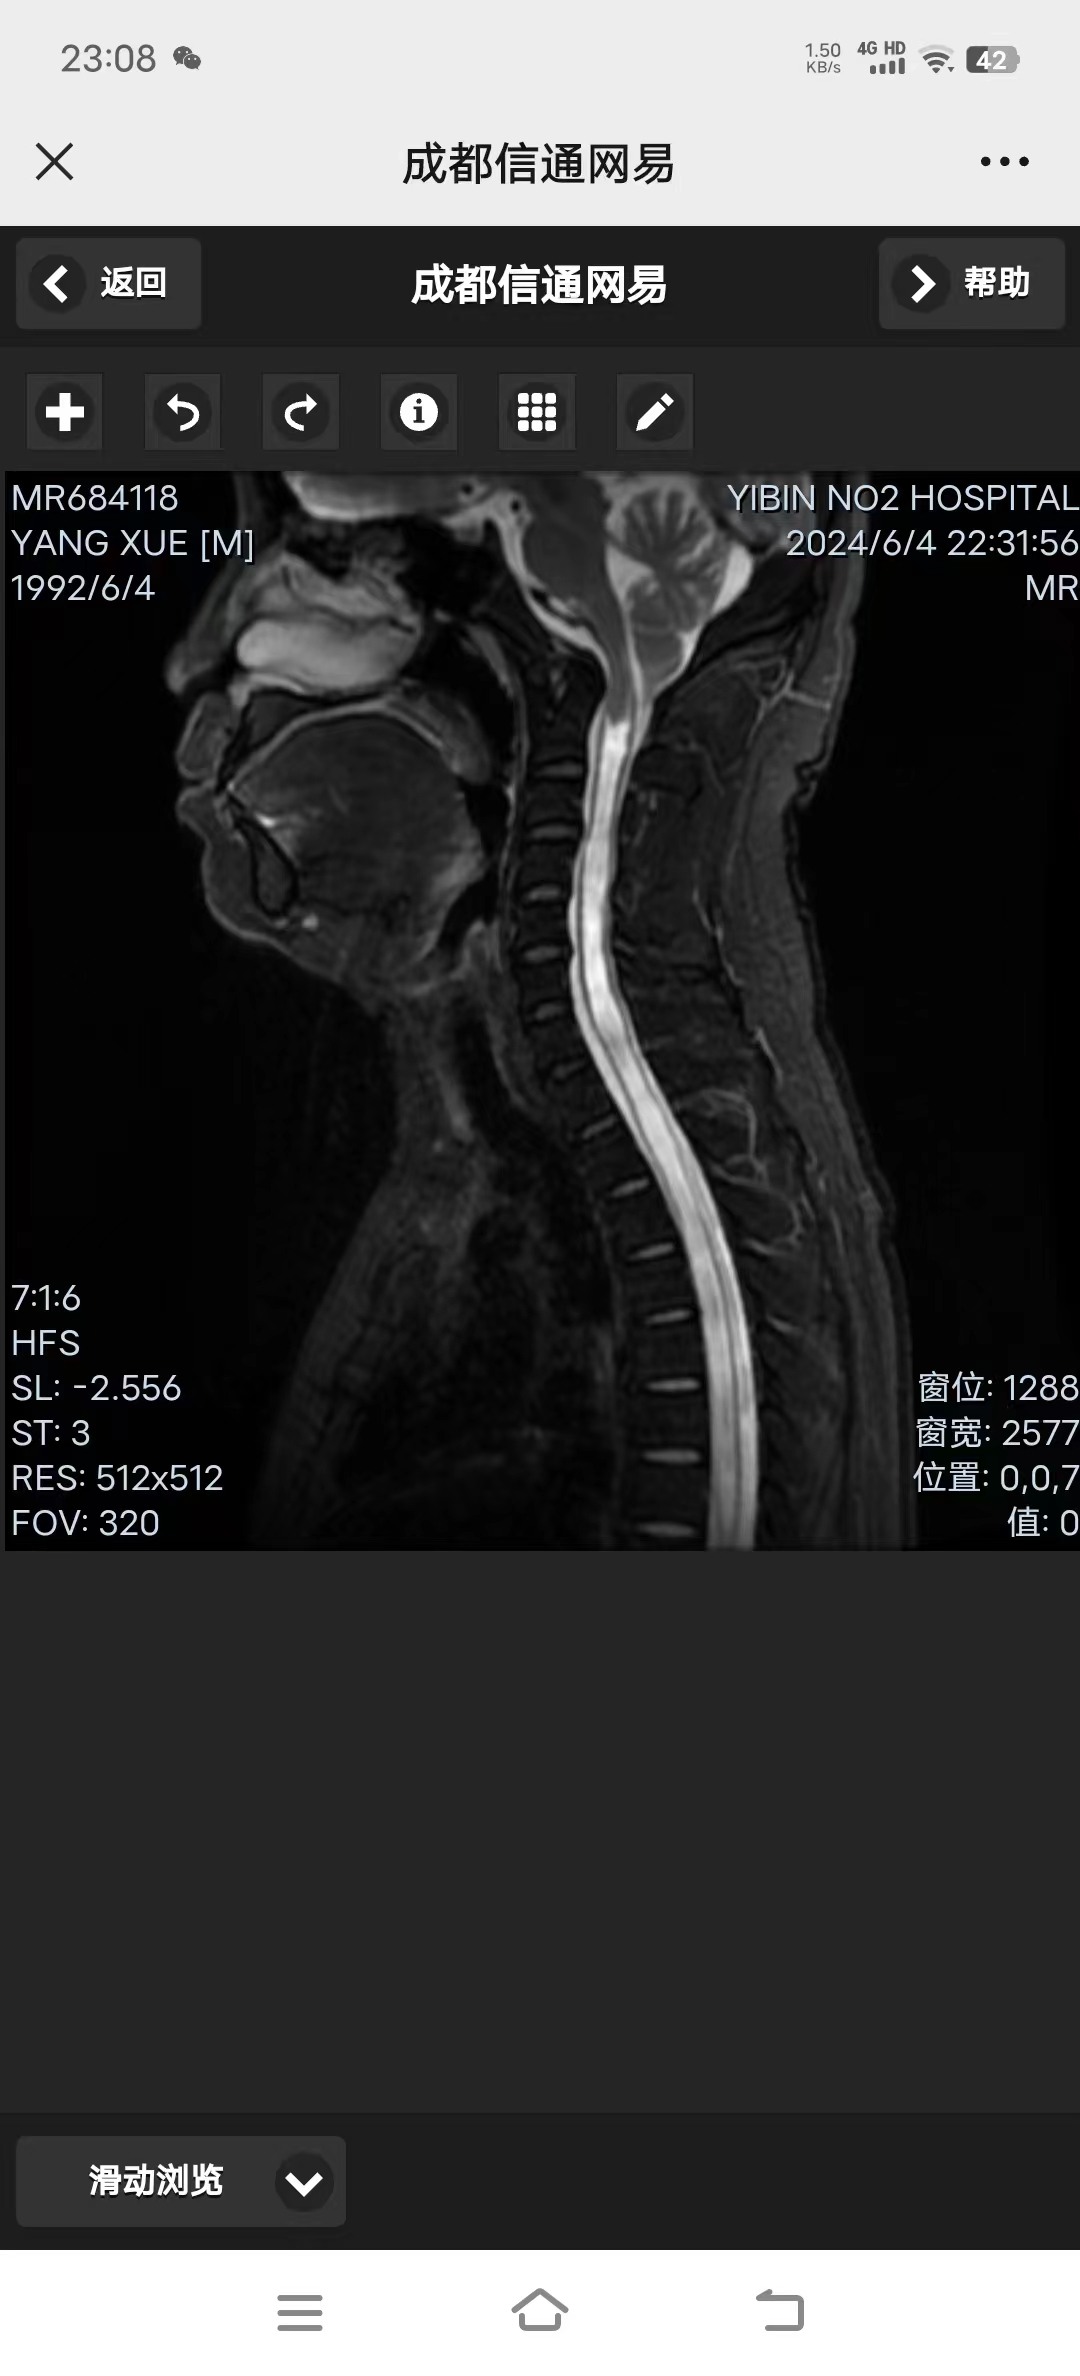

• 日期:2024.11.23

• 医院:湘雅三

• 主刀:李劲松

• 术后影像:

• 第二天下床,术后15天,头不晕了,走路稳了,左手力量和灵活度稍有好转。